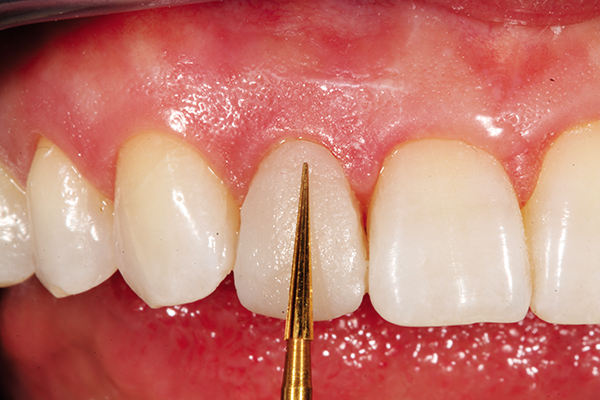

A patient with a very compromised cardiovascular condition wanted to conservatively improve her smile at tooth #7, where it was dark from retrusion and old compositematerial that was poorly shaped. To correct this matter, a strategy to whiten the surrounding teeth while a blueprint of an improved shape/volume was created on a model would be followed by gently reshaping line angles and doing a direct veneer on the challenging tooth (Fig. 6).

Fig. 6 Fig. 7

Tooth #7 was conservatively prepared to remove old composite buccally and interproximally. After microetching with aluminum oxide and rinsing with chlorhexidine, 37% phosphoric acid was applied and rinsed thoroughly with water and then lightly dried.